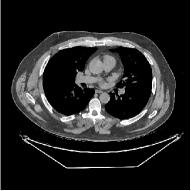

This section compares the generalization capabilities between the proposed MBIR method, PWLS-ST-, and a denoising deep NN, FBPConvNet [14], that are trained from the phantom data; in particular, we tested the trained PWLS-ST- and FBPConvNet models to phantom and clinical scan data. The results in Fig. 6 show that the non-MBIR FBPConvNet method has higher overfitting risks, compared to the proposed PWLS-ST- MBIR method. When tested on clinical scan data, PWLS-ST- achieves much more accurate reconstruction, compared to FBPConvNet. See Fig. 6(b). When tested on phantom data, FBPConvNet generates more unnatural features as the number of views reduces, although it gives lower RMSE values compared to PWLS-ST-. See zoom-ins in Fig. 6(a). The FBPConvNet results above correspond to those in the recent work [16] that FBPConvNet [14] generated some unexpected structures.

Fig. 7 studies the influence of regularization parameters and on PWLS-ST-. Given a fixed hard-shrinkage parameter , a larger value better removes noise (or unwanted artifacts), but too large can oversmooth reconstructed images; compare Fig. 7(a) and Fig. 7(b). Given a fixed regularization parameter , a larger value leads to lower sparsity in sparse codes and achieves better noise reduction, but too large can remove some edges (e.g., in bone regions); compare Fig. 7(c) and Fig. 7(d). In particular, Fig. S.8 in the supplement shows that once the value is properly chosen, PWLS-ST- is robust to a wide range of values.